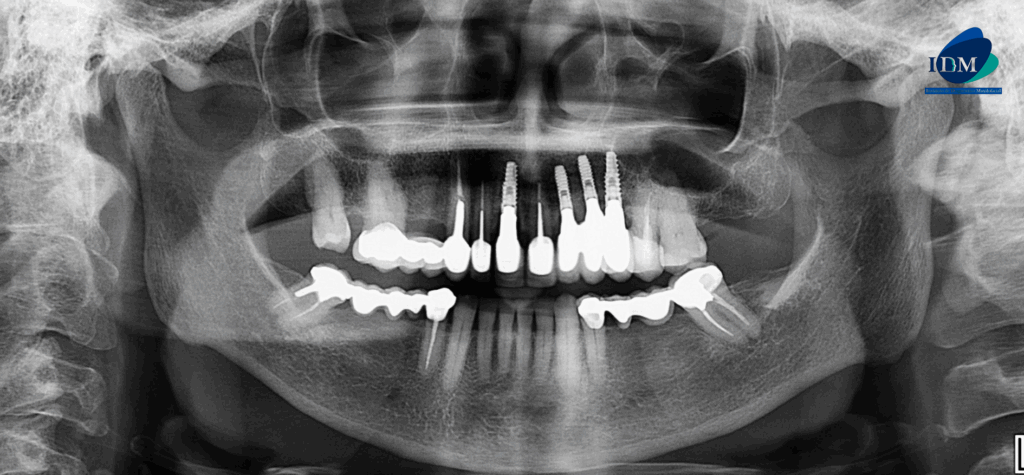

En la radiografía panorámica (Figura 1), se observa edentulismo parcial, múltiples restauraciones protésicas e implantes dentales. Además de un aumento de la densidad ósea en zona de paladar.

A la evaluación de la tomografía volumétrica (cone beam) bimaxilar en los cortes axiales (Figura 2) y transaxiales (Figura 3) se observa imagen hiperdensa de densidad ósea y forma bilobular localizada en en zona de paladar duro a nivel de línea media

- Torus palatino